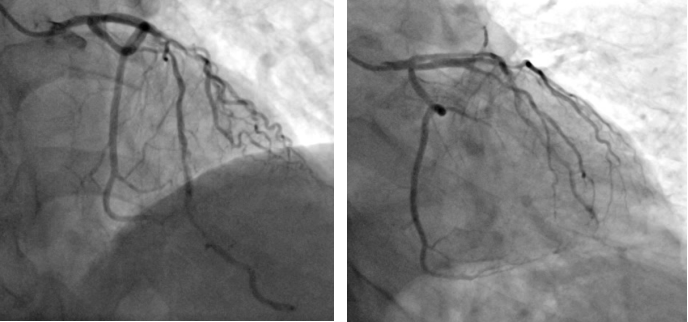

术前造影

患者为一名67岁的男性,于一月前因“反复活动后胸痛5年”入院,于右冠脉植入支架一枚。术后患者活动后胸痛较前未见明显缓解。11月9日患者返院,心血管内科二病区根据病人情况,再次为患者行PCI治疗。术中因尝试使用“预扩张球囊”于病变处扩张后效果差,但再次使用“切割球囊”于病变处切割后依旧可见钙化斑块难以充分扩张。通过血管内超声(IVUS)可见左前降最小管腔面积仅1.8mm2,深层大于270°环形钙化斑。